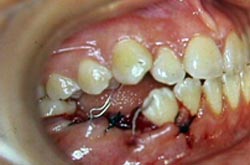

Al examen clínico se observa (Figuras 1,2,3,4,5)

• leve y generalizada inflamación de las encías, que se manifiesta con cambios de coloración

• perdida de sustancia calcificada en 17, 36, 37, 46 y 47

• presencia de dientes primarios: 84, 85

• presencia de supernumerarios entre 17-16 y 26-27 (vestibular)

• mordida cruzada entre 12-43 y 24-44

• ruido articular derecho sin sintomatología

• no presenta guía canina del lado de trabajo derecho.

FIGURA 1 Foto Intrabucal lateral derecha